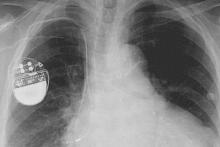

کارشناسان امنیتی هشدار می دهند که هکرها می توانند با نفوذ به دستگاه های تنظیم ضربان قلب که در داخل بدن انسان کار گذاشته می شود، زندگی این بیماران را به خطر بیندازند.

به گزارش سیتنا به نقل از گیزمودو، بسیاری از تجهیزات پزشکی مبتنی بر فناوری اطلاعات مانند پمپ های تزریق انسولین و دستگاه های تنظیم کننده ضربان قلب از آسیب پذیری هایی برخوردار هستند که دستکاری آنها برای هکرها را ممکن می کند.

محققان شرکت امنیتی وایت اسکوپ می گویند دستگاه های تنظیم ضربان قلب ۴ شرکت مشهور سازنده این نوع تجهیزات و همین طور سیستم های مورد استفاده برای کنترل و بررسی عملکرد دستگاه های یاد شده در مجموع دارای ۸۰۰۰ آسیب پذیری مختلف هستند و این تعداد بی سابقه از اشکالات بسیار نگران کننده است.

کارشناسان وایت اسکوپ می گویند سیستم های نرم افزاری تولیدات هر چهار شرکت قدیمی و به روز نشده بوده و اطلاعات خصوصی مربوط به هر بیمار به طور رمزگذاری نشده بر روی آنها ذخیره می شود. لذا در زمان اتصال آنها به سیستم های نظارتی بدون نیاز به ورود کلمه عبور می توان به این اطلاعات دسترسی پیدا کرد.

این اولین بار نیست که هشدارهایی در مورد امنیت پایین تجهیزات حساس پزشکی منتشر می شود. در سال ۲۰۱۳ هم هکری به نام بارنابی جک از فاصله ۱۵ متری توانسته بود شوکی مرگبار به یک دستگاه کنترل ضربان قلب وارد کند، اما شرکت های سازنده این نوع تجهیزات هشدارهای یاد شده را جدی نمی گیرند.